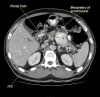

Foramen of Winslow hernia is a rare surgical entity with very few reported cases in literature. Preoperative diagnosis used to be difficult but with emerging computed tomography technology, diagnosing this internal abdominal hernia has become easier. We present an unusual case report of foramen of Winslow hernia in a 77-year-old patient who presented with severe abdominal pain. The patient underwent laparoscopic repair of the hernia and recovered well postoperatively. This presentation of symptoms in a 77-year-old male is unusual and laparoscopic management of foramen of Winslow hernia presents an interesting and challenging management scenario.